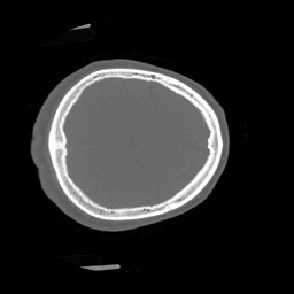

Model-based treatment planning for transcranial ultrasound therapy typically involves mapping the acoustic properties of the skull from an x-ray computed tomography (CT) image of the head. Here, three methods for generating pseudo-CT images from magnetic resonance (MR) images were compared as an alternative to CT. A convolutional neural network (U-Net) was trained on paired MR-CT images to generate pseudo-CT images from either T1-weighted or zero-echo time (ZTE) MR images (denoted tCT and zCT, respectively). A direct mapping from ZTE to pseudo-CT was also implemented (denoted cCT). When comparing the pseudo-CT and ground truth CT images for the test set, the mean absolute error was 133, 83, and 145 Hounsfield units (HU) across the whole head, and 398, 222, and 336 HU within the skull for the tCT, zCT, and cCT images, respectively. Ultrasound simulations were also performed using the generated pseudo-CT images and compared to simulations based on CT. An annular array transducer was used targeting the visual or motor cortex. The mean differences in the simulated focal pressure, focal position, and focal volume were 9.9%, 1.5 mm, and 15.1% for simulations based on the tCT images, 5.7%, 0.6 mm, and 5.7% for the zCT, and 6.7%, 0.9 mm, and 12.1% for the cCT. The improved results for images mapped from ZTE highlight the advantage of using imaging sequences which improve contrast of the skull bone. Overall, these results demonstrate that acoustic simulations based on MR images can give comparable accuracy to those based on CT.